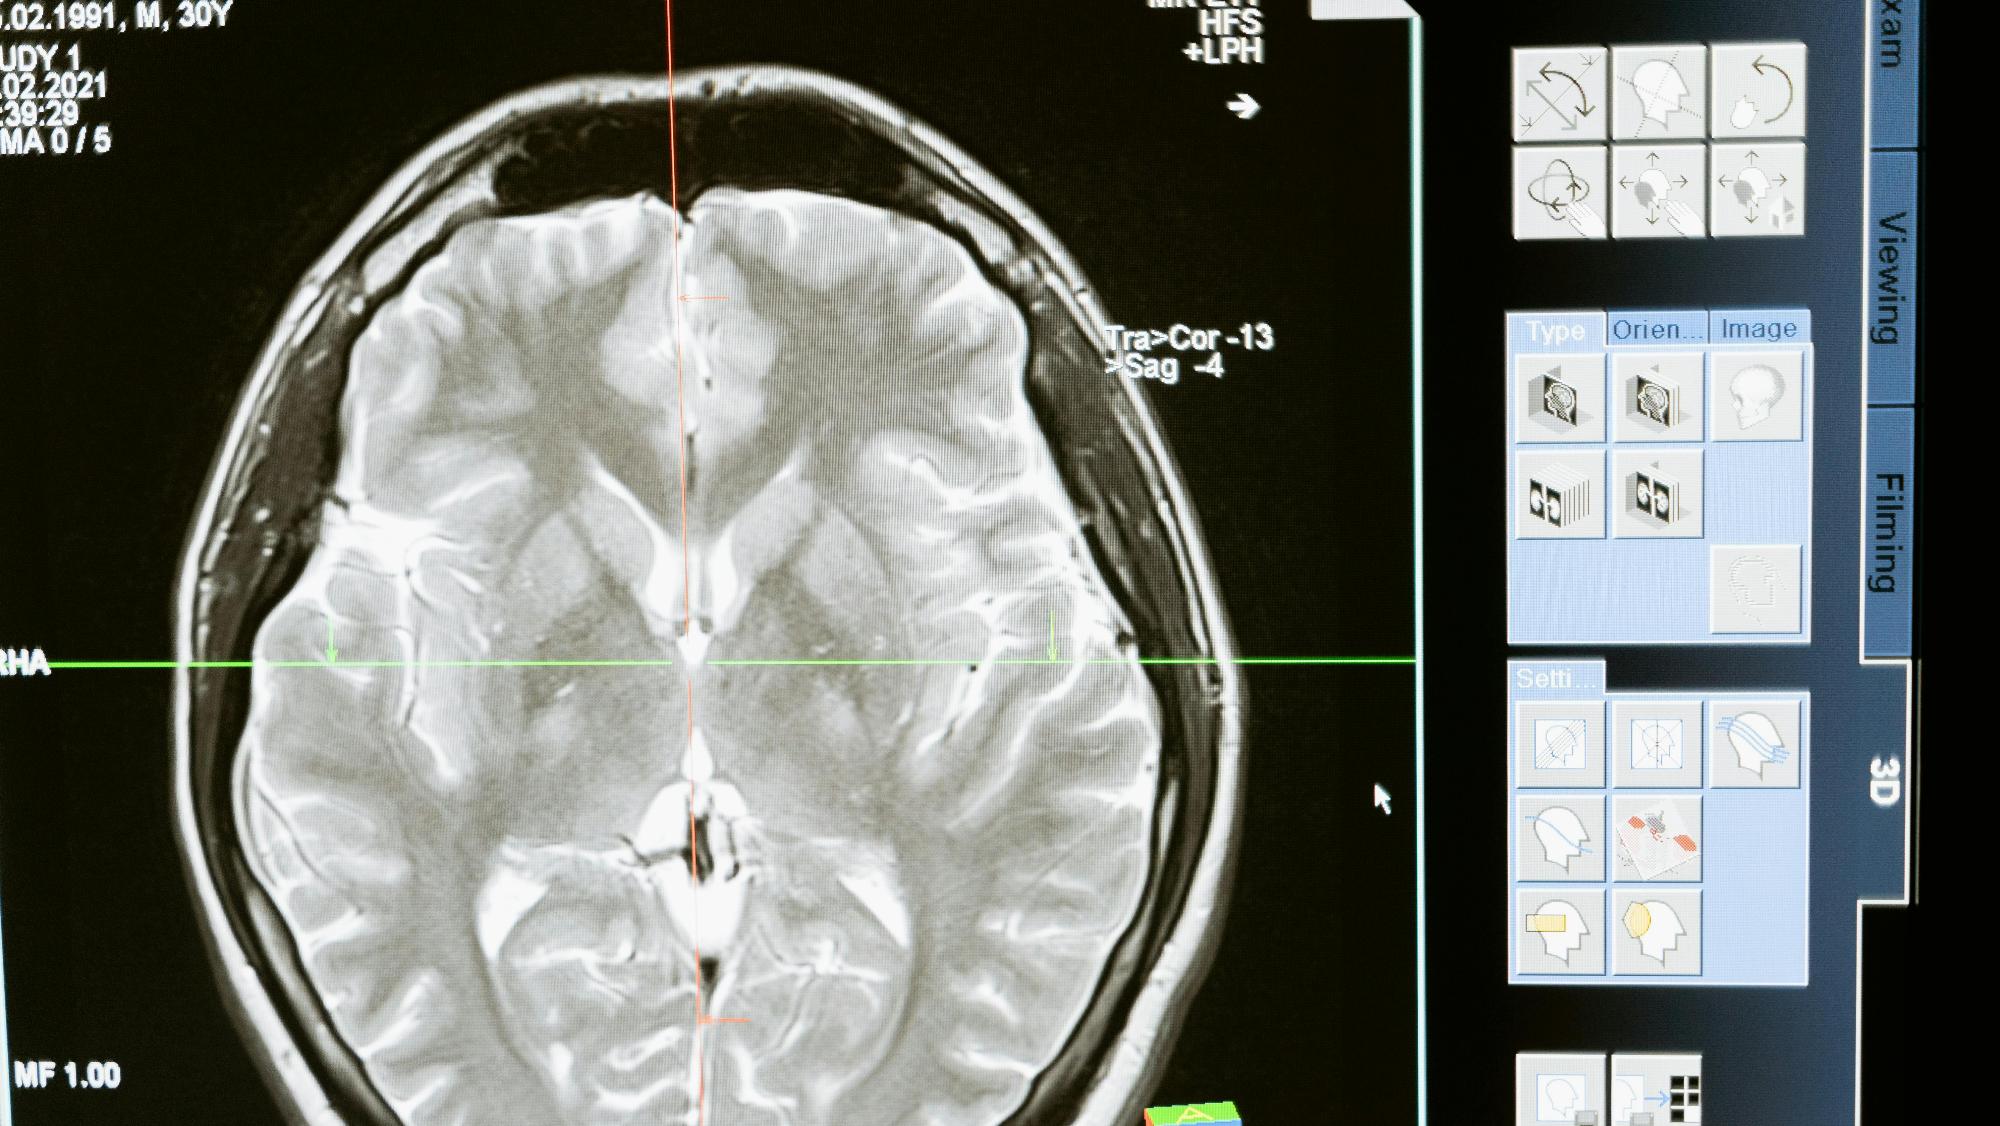

• Методы радиологических исследований и диагностики;

• Основы лучевой диагностики, методы, техника безопасности;

• Лучевая диагностика при заболеваниях органов и систем;

4. Использовать и интерпретировать результаты исследования КТ, МРТ и по ядерной медицине, оценивать риски радионуклидного исследования. Протоколы сканирования, технологии контрастирования, сцинтиграфия. Радионуклидная диагностика эндокринной, сердечно–сосудистой, костно-суставной системы, патологии печени и почек.